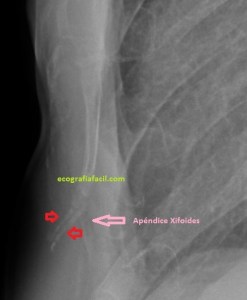

Con la eco pasa igual…cuando queremos estudiar, por ejemplo, el recto anterior del muslo en axial,perfecto…pero en longitudinal, como la imagen 2, se complica porque desde la rótula a la inserción en la cadera, tenemos mucho recorrido. En este caso hacemos lo mismo que cuando hacemos la foto del atardecer…nos ponemos en un extremo, activamos la funciona, recorremos suave y continuamente por la anatomía que queremos fotografiar y ya está…mira la pantalla y no el movimiento de tu mano,como si hicieses la foto, ves la pantalla,pero no como mueves el teléfono.

Es muy útil para lesiones que han crecido mucho y no podemos conjugar en una sola imagen, por ejemplo, un lipoma, cuando superan la medida de la huella de la sonda no son medibles, hay que usar «panoramic view», y como este caso, otros muchos.

En la imagen 3 ves una imagen de un lipoma, mide 7 cms, la huella de la sonda mide 5cms, la «panoramic view» posee una regla centimetrada que sigue el contorno de la imagen, justo en la profundidad de la misma y lo marca la flecha amarilla. La profundidad la marca la flecha roja y la flecha blanca marca el rango centimetral de los 5cms, fíjate que la línea blanca es ligeramente mayor cada 5 cms. Sirve de referencia, como en la imagen 4 donde ves una colección en el glúteo de más de 10 cms.

Técnicamente es lo mismo, ambos dispositivos hacen una suma de imágenes que se plasman en un resultado final estupendo. Toda la escena más pequeña, pero más alargada que te da percepción de toda la magnitud de aquello que pretendes estudiar, te quita algo de detalle, pero te sirve para medir perfectamente y además puedes incrementar y mover la imagen con tu track ball…

Podemos medir valores superiores a los 15cms con alta calidad de imagen…podemos llegar a medir valores por encima de los 25 cms…es verdad que no todos los equipos tienen este ajuste ecográfico, es decir, es una aplicación y por tanto hay que pagarla.